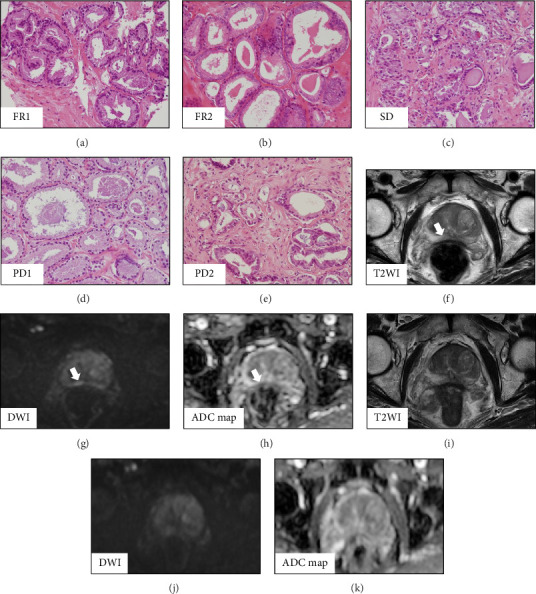

Background: A need exists for effective treatments for prostate cancer (PCA) due its re-emergence following androgen deprivation therapy, a major clinical problem. In a previous study, we presented evidence on the chemopreventive and chemotherapeutic potential of luteolin, a flavonoid, in PCA including castration-resistant PCA. In this single-arm phase I study, we clinically examined the safety of the oral intake of luteolin in patients under active surveillance (AS). Methods: Between March and September in 2022, five patients with low-intermediate risk PCA and under AS were treated daily with 50 mg of oral luteolin for six months. We investigated the efficacy of oral luteolin in oncological outcomes and any adverse events (AEs) and examined prostate and blood specimens. Results: The median age of patients was 68 years (range: 60-78), and the median initial prostate-specific antigen level was 9.5 ng/mL. All patients were under AS without rapid progression. After treatment with luteolin, AEs were not noted in any patients for six months. All patients underwent a protocol biopsy. Of these, two patients showed a favorable response, one patient had stable disease, and two patients showed disease progression; robot-assisted radical surgery was subsequently performed for the latter. Immunohistochemical analysis revealed decreased expression of androgen receptor and NKX3.1 in noncancerous lesions after luteolin treatment. In addition, quantitative reverse transcription-PCR revealed that serum micro(mi)RNA expression in serum and prostate gland, including miR-29 and miR-30, tended to be upregulated after luteolin treatment compared with during the pretreatment phase. Conclusions: Our small phase I study of men with PCA suggests that daily treatment with 50 mg of an oral supplement of luteolin is safe and effective with regard to oncological outcomes, particularly in patients under AS.